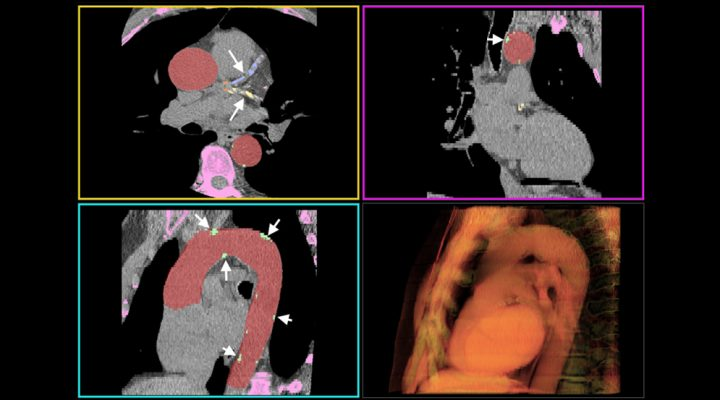

“En pacientes con indicios de enfermedad cardiovascular, la detección del calcio coronario y aórtico con imágenes de tomografía ha demostrado ser una herramienta efectiva para mejorar la prevención temprana. Nuestro sistema con IA detecta y mide de forma rápida y precisa el calcio que figura en esas imágenes”, explica Craiem.

El calcio vascular se observa en las tomografías como manchas blancas que aparecen en los bordes de las paredes arteriales. Para medirlo, el radiólogo utiliza generalmente un software que le permite explorar plano a plano el corazón y las arterias, resaltar los candidatos que pueden ser potenciales lesiones y luego hacer clic sobre cada uno para validarlos.

“Un paciente puede tener decenas de calcificaciones y este procedimiento suele ser largo y tedioso. Nuestro proyecto consistió en entrenar un software para que primero aprenda a reconocer la aorta donde se forman las calcificaciones y luego busque potenciales lesiones y decida cuáles son verdaderas. En un par de minutos el sistema de IA entrega las mediciones de calcio que a un radiólogo a veces puede llevarle entre 15 y 30 minutos”, puntualiza Craiem. Y agrega: “En resumen, el sistema basado en IA permite medir automáticamente un score de calcio torácico. Como el riesgo de los eventos cardiovasculares está asociado a la cantidad de calcio en las arterias, esta herramienta automática ayuda a los cardiólogos a mejorar los tratamientos preventivos”.

“En medicina lo más ético es interesarse sobre los errores del sistema y no sólo sobre sus aciertos. ¿Qué sucede con ese 5% de error? ¿Cuántos pacientes son? ¿Qué consecuencias puede provocar el error de medición sobre el diagnóstico de esas personas? Nuestro sistema fue diseñado para que, en caso de cometer un error, lo haga hacia arriba. Es decir, sobrestimando la cantidad de calcio y nunca subestimando. Esto permite que, en el peor de los casos, el sistema informe un valor de calcio mayor al que corresponde y que el médico pueda evaluar y corregir la medición”, explica Craiem. Y continúa: “Nuestro sistema está diseñado no sólo para calcular el score de calcio e informar un número, sino para que el radiólogo pueda ver en pantalla las calcificaciones detectadas y dar su opinión sobre la detección”.